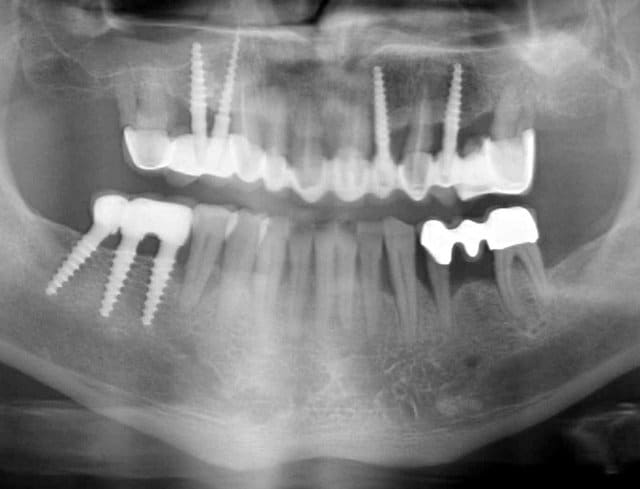

Bonjour flicflac je suis désolé de ma réponse tardive, oui il est vrai que ce n est pas beaucoup documenté ... je serai un menteur de dire que que je n ai jamais perdu des implants, surtout entre la 2eme et 8eme semaine après l implantation.Un échec vraiment à cause de la perte osseuse et avec le même process cela est arrivé une fois avec une madame, où l´os était encore infecté ( avant la chirurgie),mais après l ´échec (c était à la position 35) on a pu laisser le bridge. Malheureusement je n ai pas toutes les photos ici à Mallorque sur mon PC portable. Ci dessous une photo après 10 ans 46 47 et les implants au maxillaire.

Oui ca semble ....sur la opg radio tu peux voir la situation seulement deux semaines après l´implantation immédiate 34 jusqu´à 36 et 45, les derniers 2 photos montrent la même situation après un an ( où on a enlevé la supra construction pour un contrôle). Sur ce cas je voulais montrer la bonne régénération osseuse et de la gencive.

Voilà une patiente que je revois à deux ans apres la pose d'un monobloc Classic line 3,5/12mm et prep cap zircone 12 degres 2/2 en 24.

Radios 1,2,3 photo 1= jour de la pose de l'implant.

radio 4 photo 2 et 3= 8 semaines post pose de l'implant, ceramiques scéllées.

Radio 6, photo 4 et 5 controle à 24 mois.

Deux ans plus tard, la gencive a recouvert la zircone et on observe à la radio un gain osseux au niveau des micros spires.